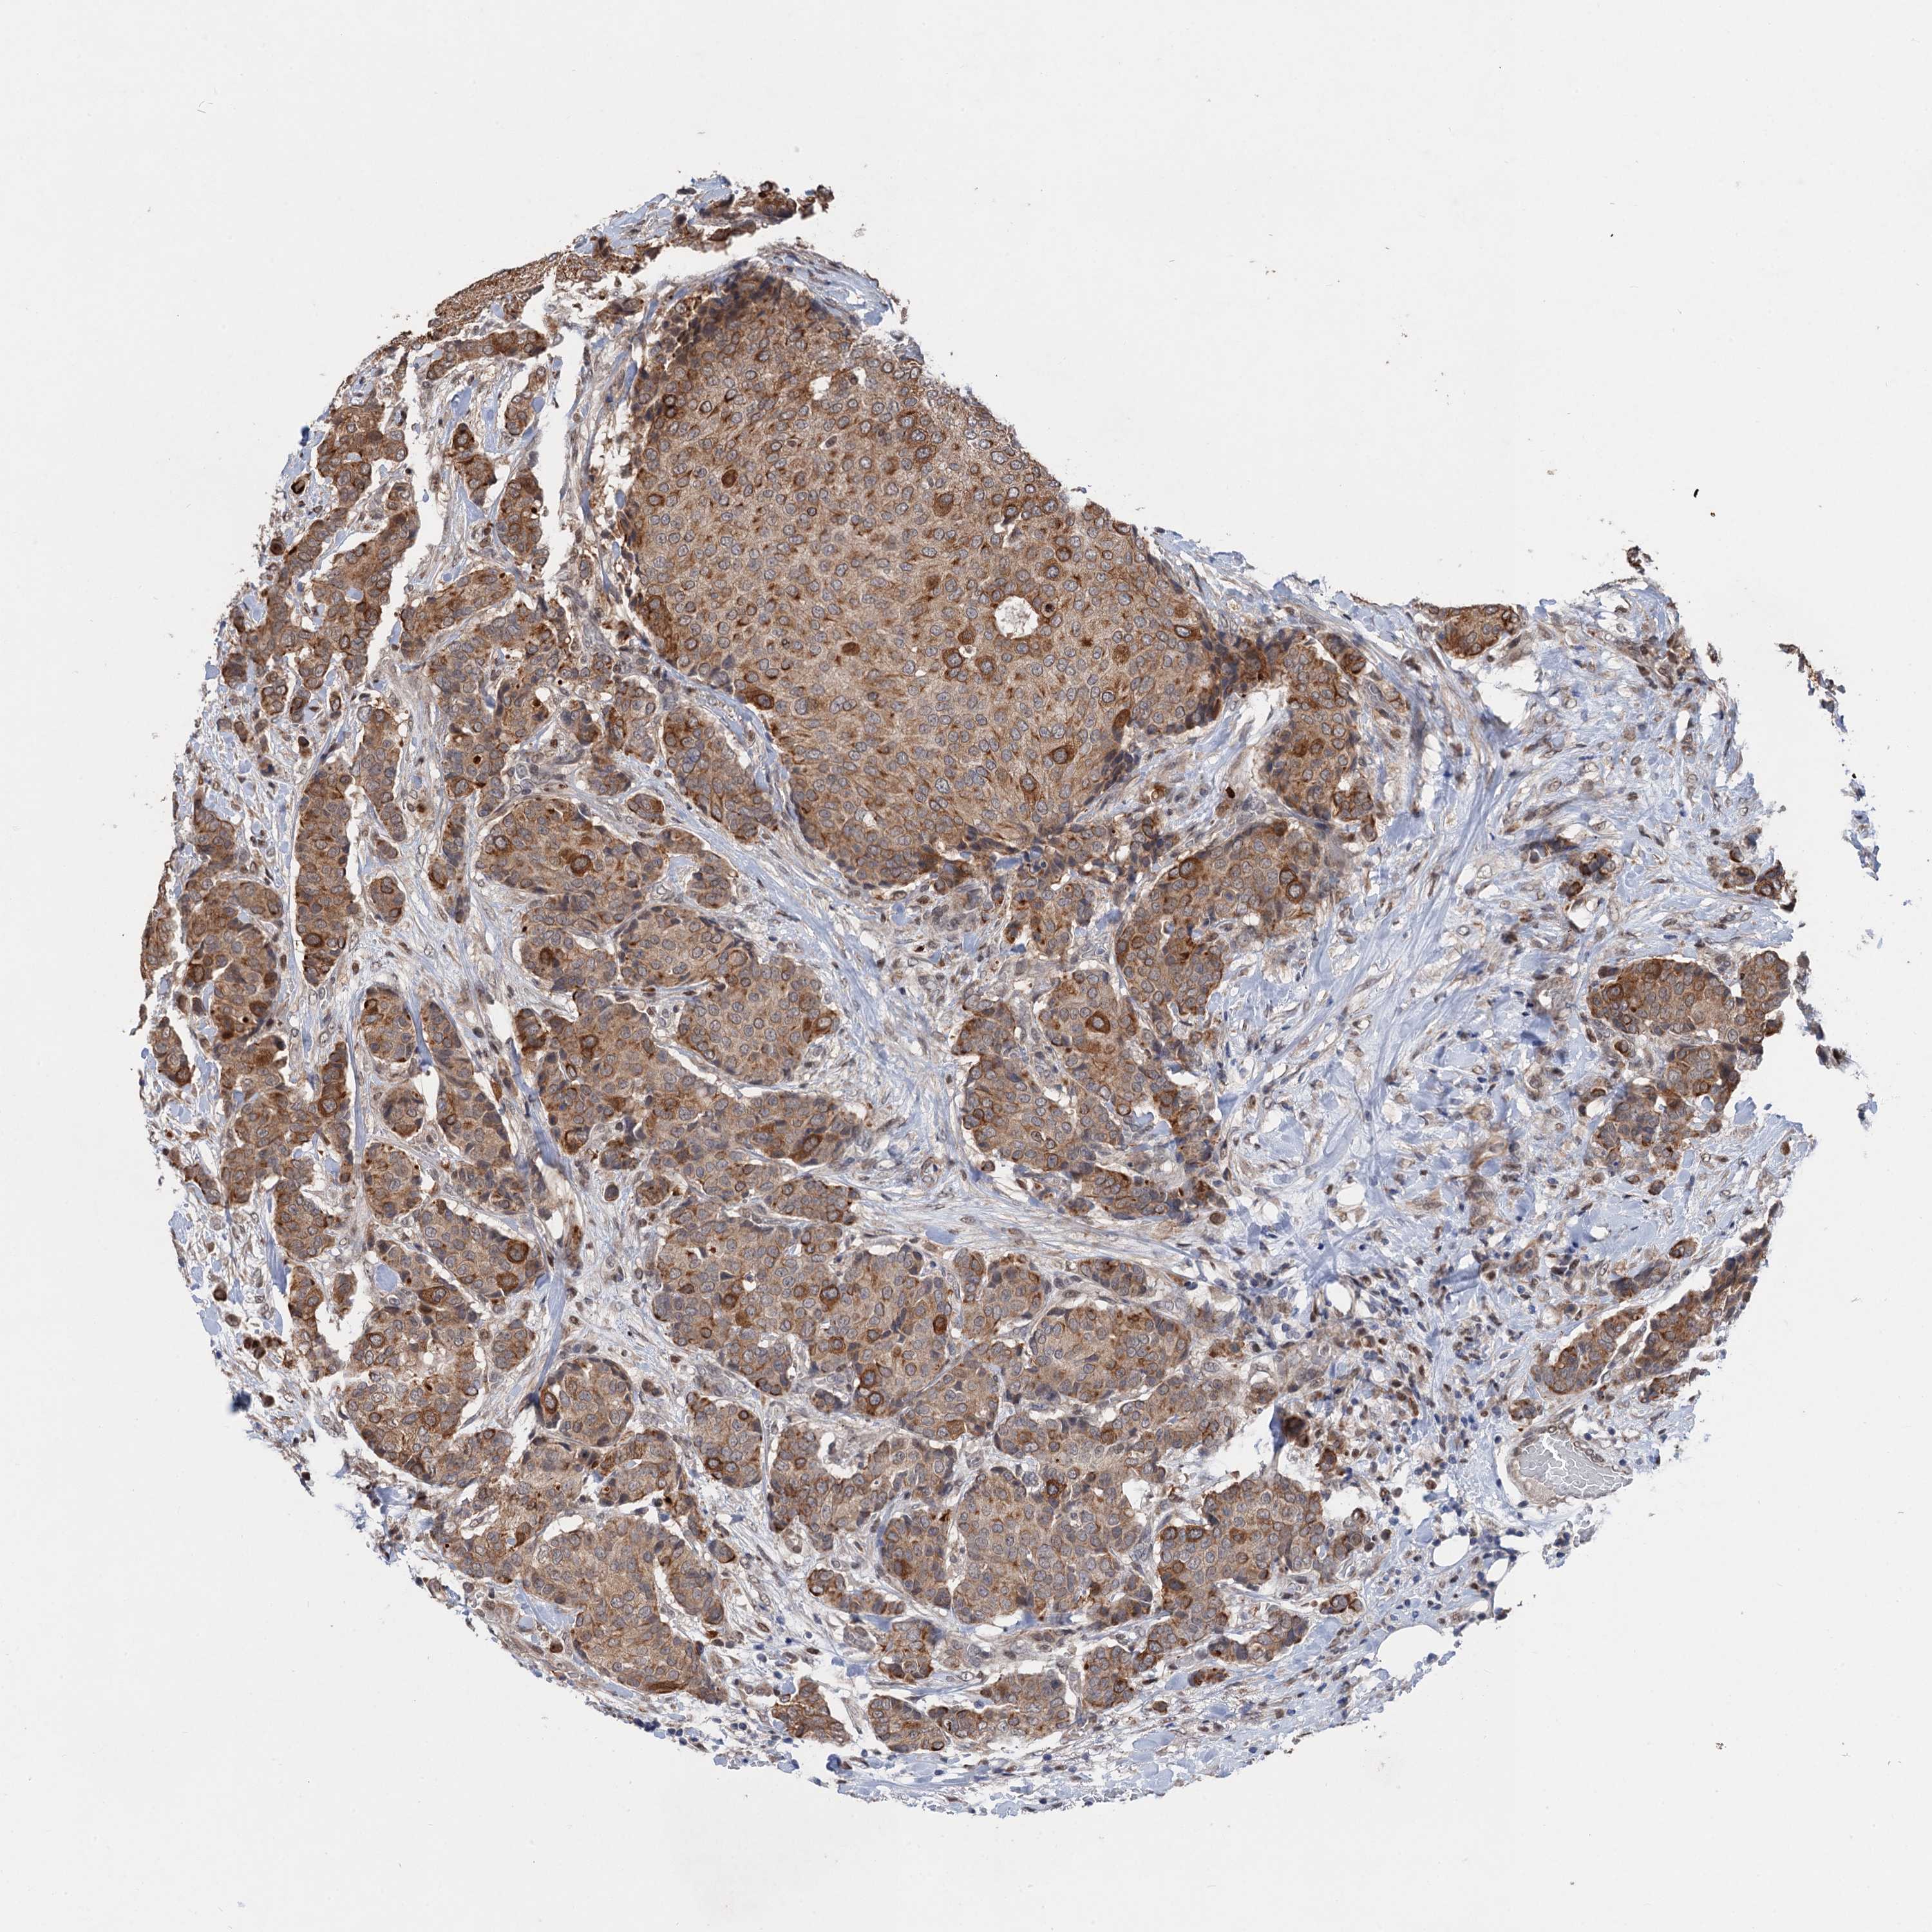

CANCER BREAST CANCER Show tissue menu

BRCA TCGA BRCA VALIDATION PROTEIN EXPRESSION